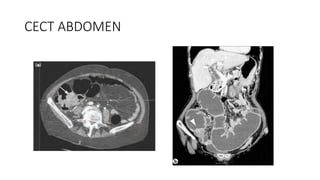

• CECT ABDOMEN

CECT ABDOMEN